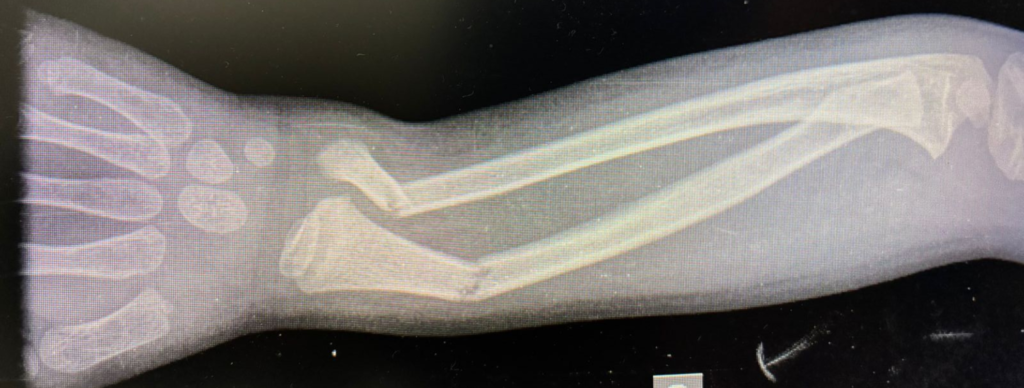

Fratura fechada

Fratura deslocada

Fratura em “galho verde”

Fratura aberta ou exposta

Fratura subperiostal

Fratura frisária